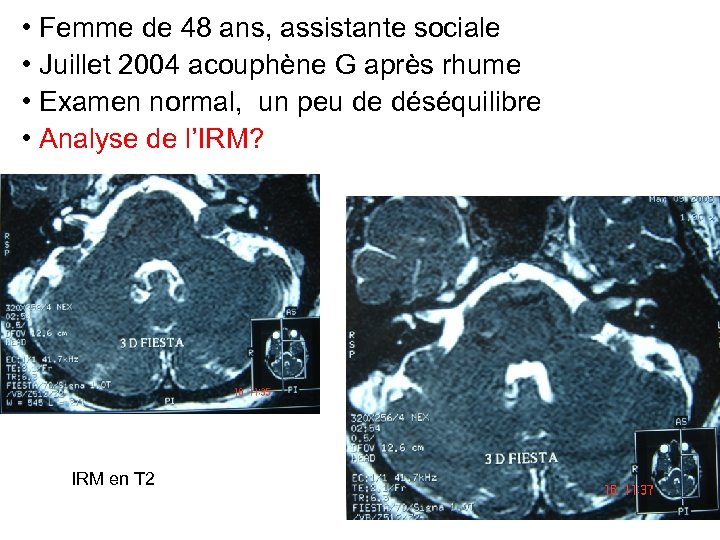

• Femme de 48 ans, assistante sociale • Juillet 2004 acouphène G après rhume • Examen normal, un peu de déséquilibre • Analyse de l’IRM? IRM en T 2

• Femme de 48 ans, assistante sociale • Juillet 2004 acouphène G après rhume • Examen normal, un peu de déséquilibre • Analyse de l’IRM? IRM en T 2

Analyse de l’IRM • Volume, taille, stade de tumeur • Vacuité du CAI • Place du canal semi circulaire postérieur

Analyse de l’IRM • Volume, taille, stade de tumeur • Vacuité du CAI • Place du canal semi circulaire postérieur